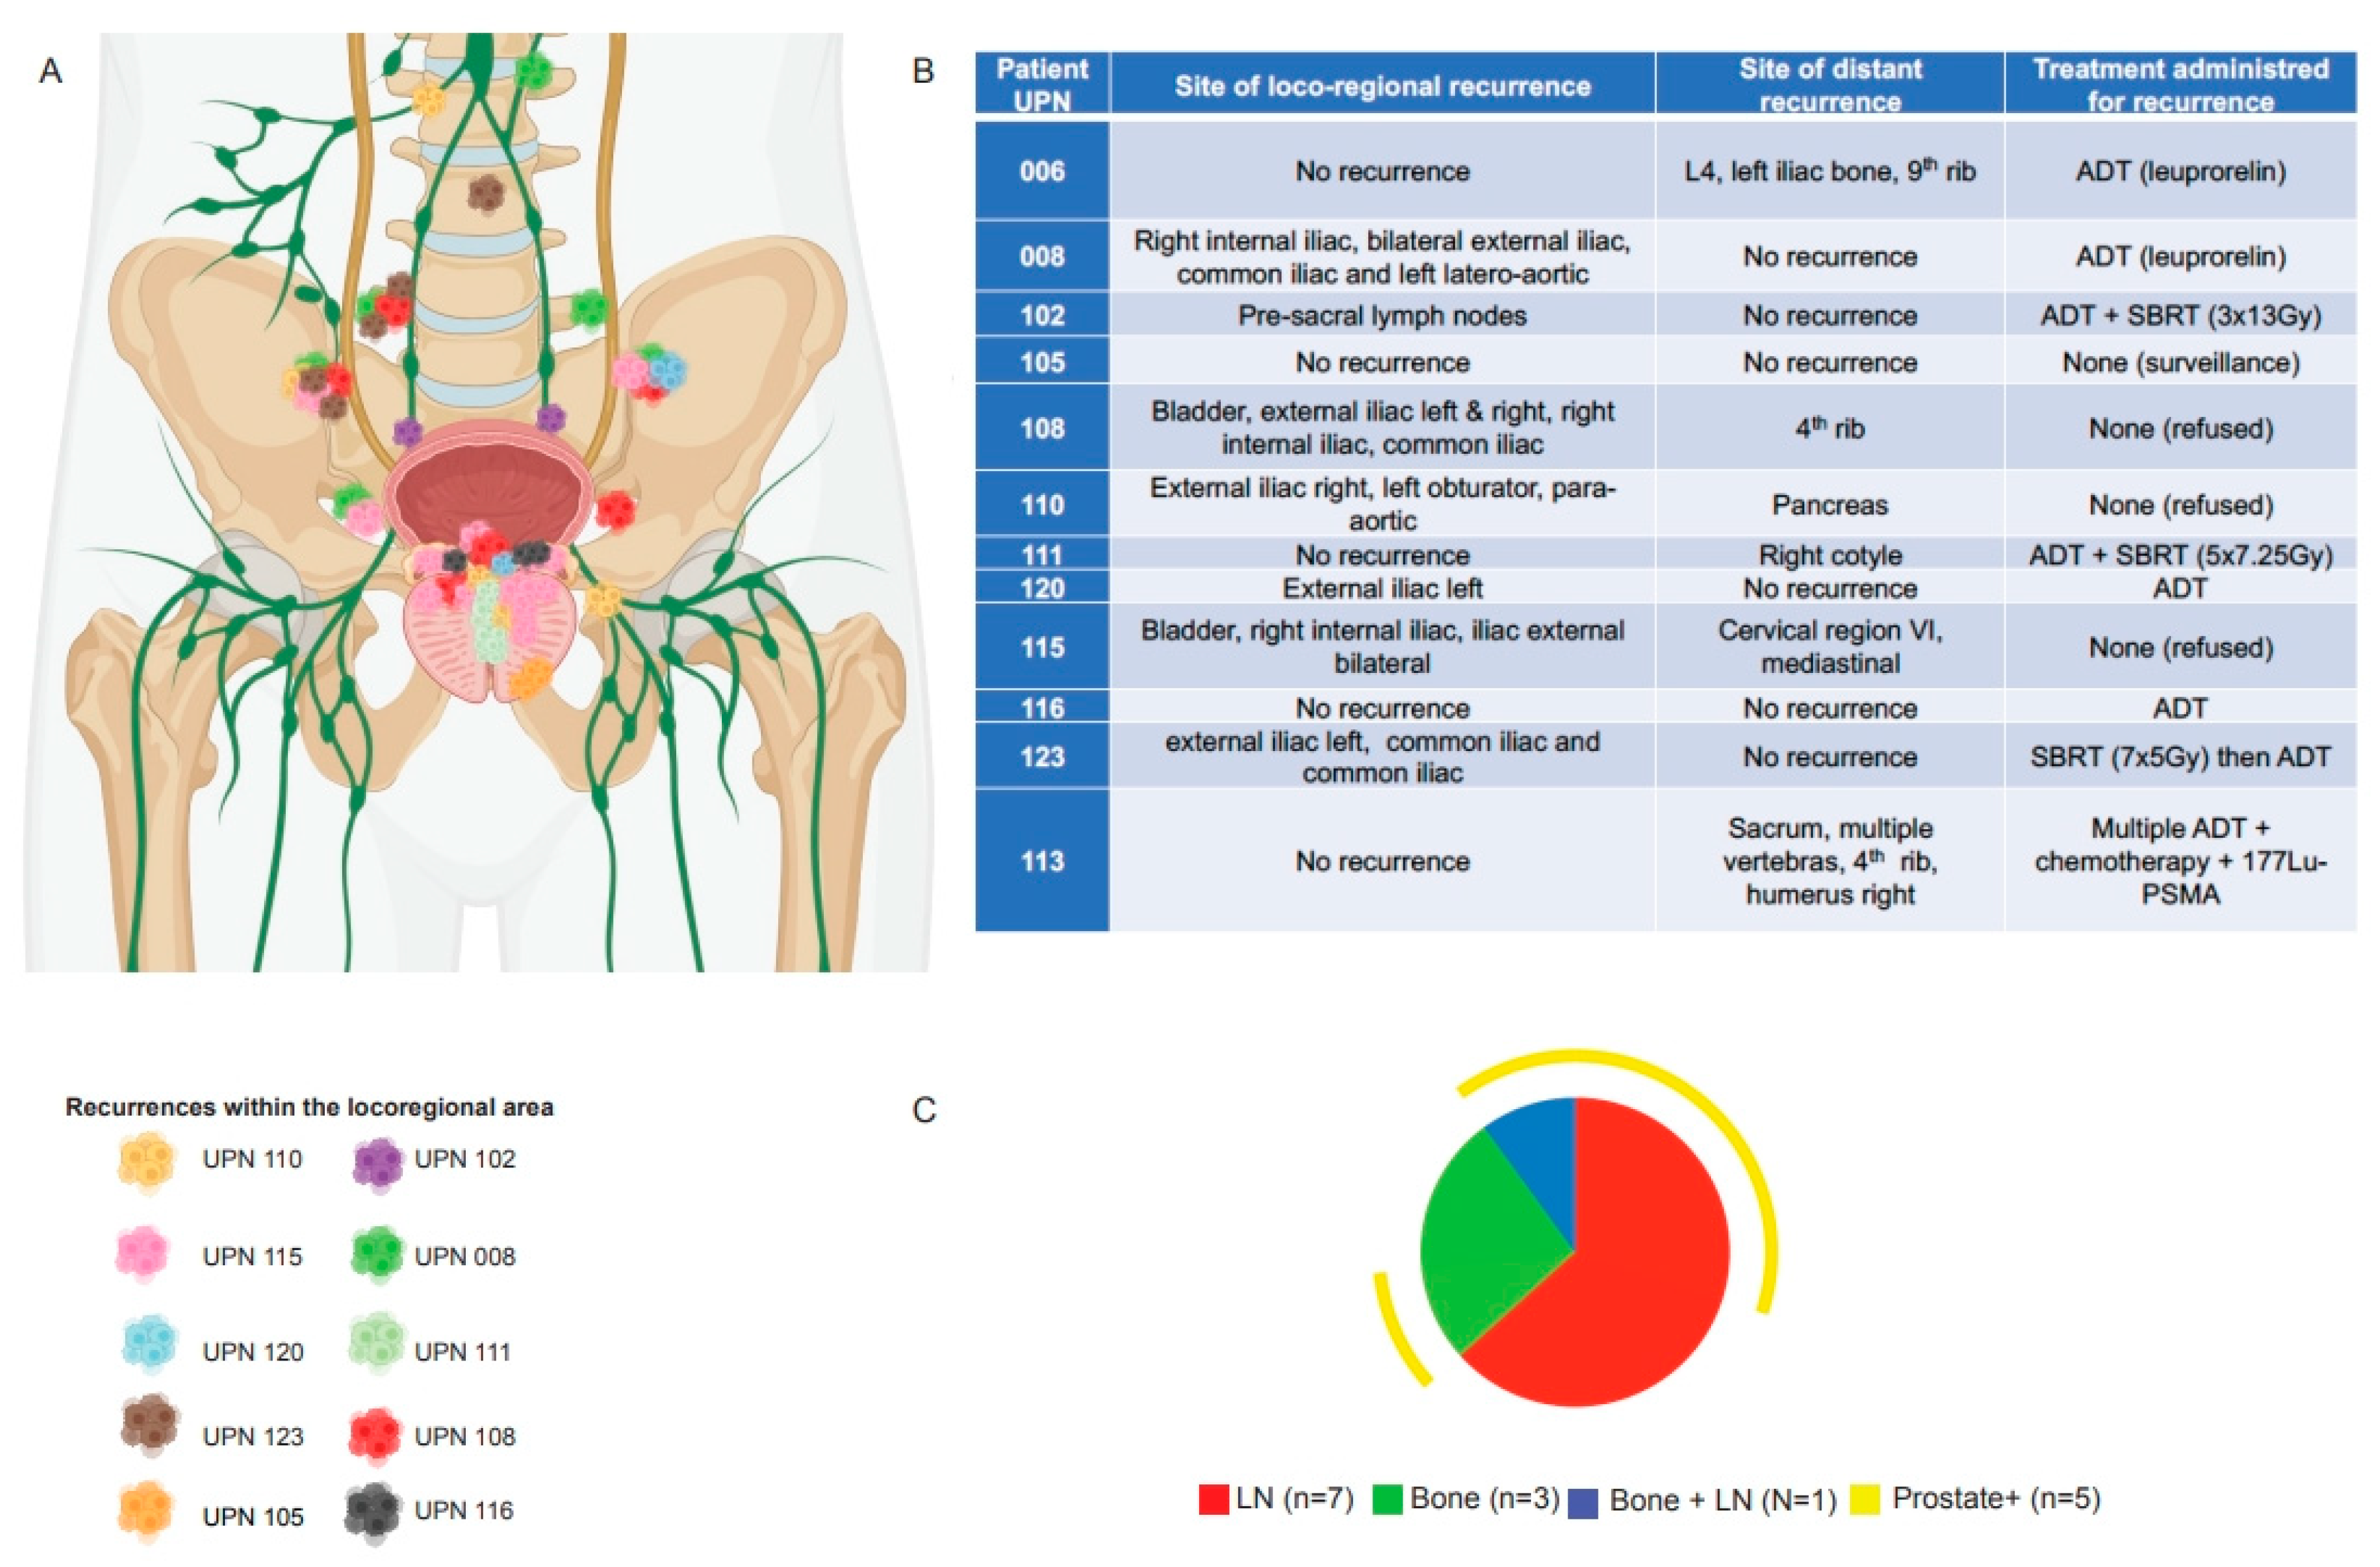

3.1. Pattern of Recurrence